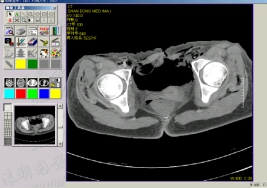

主要研究内容:(1)图像处理与模式识别。研究影像修复、超声医学图像的分割、贴壁细胞分割及识别、人脸识别、虹膜识别、基于视觉的缺陷检测、基于声音的故障诊断等。(2)人机交互技术。研究基于视觉和声音的人机交互技术、基于感知设备的多模态获取和交互技术等。(3)虚拟现实技术。研究煤矿火灾和水灾的演化机理、可视化技术、灾害解算技术、虚拟现实平台的通信和交互技术、及灾害虚拟仿真技术和培训系统。